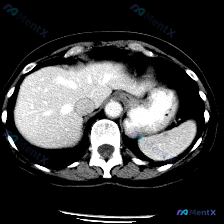

这是一幅上腹部CT软组织窗横断面图像:

- 肝脏:轮廓平整,实质密度均匀,肝内血管走行清晰,无受压移位;

- 脾脏:划重点——形态正常、大小正常、实质密度均匀,未见局灶性低/高密度影,包膜清晰,周围脂肪间隙无渗出;

- 胰腺(所见体尾部):形态清晰,边界规整,无肿块/萎缩,周围脂肪间隙清晰;

- 腹膜后及大血管:腹主动脉、下腔静脉管径正常,管腔充盈可;腹膜后及肝门区未见明确肿大淋巴结,无积液/渗出;

- 其他:胃腔内可见造影剂充盈,壁轮廓尚可。